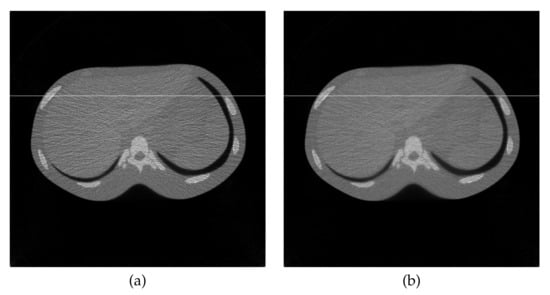

5. Conclusions